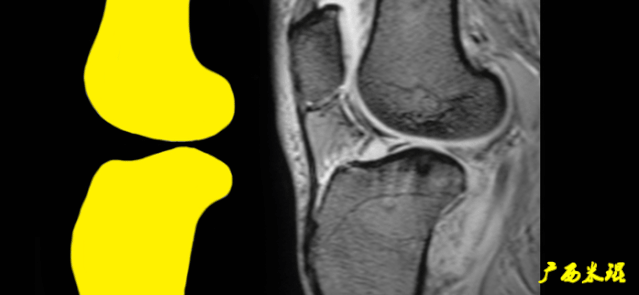

2)骨挫伤:

一旦ACL撕裂,胫骨就相对于股骨前移,使股骨外侧髁和胫骨外后方撞击,双方均出现水肿,而且膝关节屈曲的程度决定股骨髁挫伤的部位。

3)沟槽征:

当股骨外髁骨因撞击造成的凹陷深度>2mm时称为沟槽征,代表受到撞击的暴力更大。